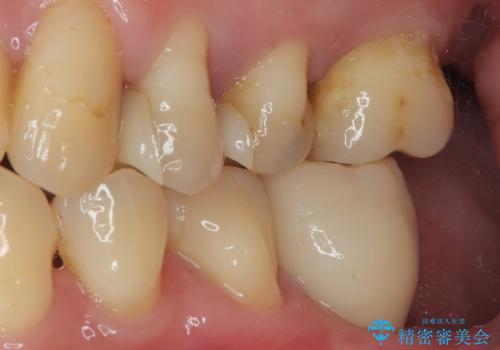

ブリッジから膿が出る 奥歯のインプラント治療

- ブリッジの土台から膿が出るとのことで来院された患者様です。

不均衡で無理な力がかかってしまうブリッジを装着したため、最後臼歯周辺の歯槽骨が溶けている状態でした。

上顎は最後臼歯が欠損しているため、ブリッジの土台は抜歯し、元々の欠損部にインプラントによる補綴治療を行うこととしました。

支台歯の骨欠損は予想以上に大きく、即時荷重インプラント部への影響が心配されましたが、無事に最短期間で治療を終えることができました。